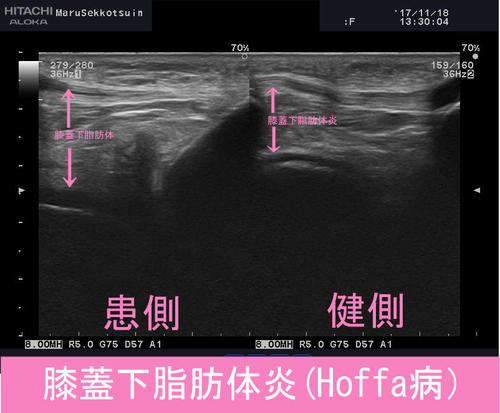

エコー検査を行ったところ、健側の脂肪体よりも大きく腫れ、

膝を動かしながら確認しても、挟まれるところも確認でき、

"膝蓋下脂肪体炎"と確定。